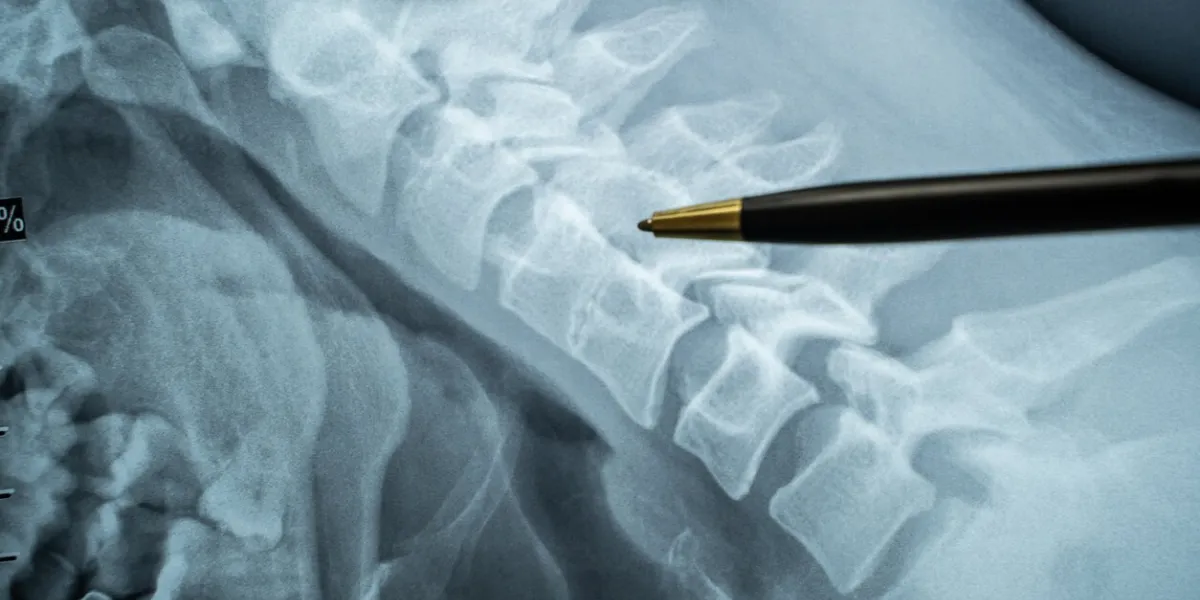

Les symptômes peuvent inclure des douleurs osseuses, des fractures spontanées ou une diminution de la taille. Les facteurs de risque incluent un faible apport en calcium, une carence en vitamine D, la sédentarité, le tabagisme et une consommation excessive d'alcool.

Un traitement précoce peut aider à ralentir la progression de la maladie et à prévenir les fractures.